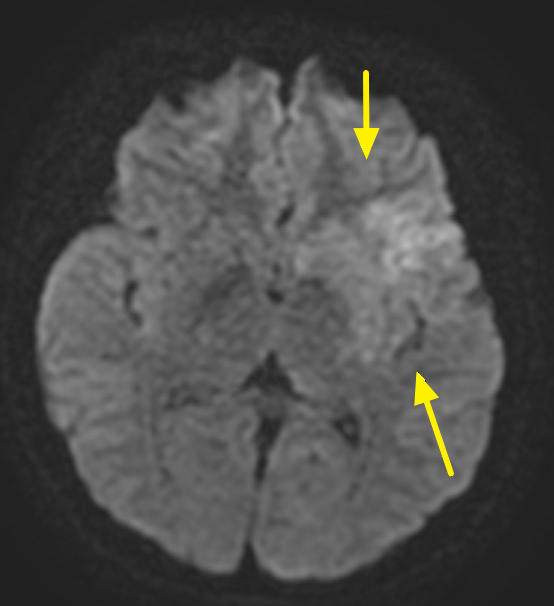

郭葉璘說明,左側大腦掌管語言中樞、身體右側活動能力及視覺與空間感知區域,中大腦動脈是負責供應大腦三分之二的重要血流。磁振造影中的擴散權重影像序列(DWI),能在中風發生後30分鐘內偵測腦部受損區域。檢查顯示該學生的左側中大腦動脈完全阻塞,磁振中的擴散權重影像序列也出現一塊淡淡的受損區域,這表示阻塞的危險性正快速提高中。若不即時處理,這片受損區域會持續擴大,腦部將因血栓壓迫而腫脹,同時往下壓迫腦幹,危及呼吸與心跳中樞,甚至造成生命危險。